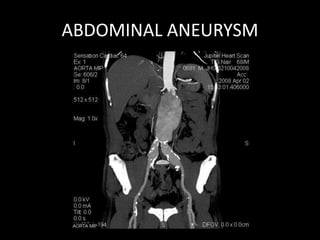

ABDOMINAL ANEURYSM

• There is extensive thrombosis of infrarenal segment of aorta, extending upto its bifurcation; into both common iliac

arteries causing total block in aorta and only minimal opacification of common ileac arteries bilaterally.

• Left renal artery is also blocked.

• Left kidney is small in size.

• Inferior mesenteric artery is not opacified.

• Bilateral external and internal iliac arteries reveal good contrast opacification from collateral of lumbar, intercoastal

and inferior epigastric arteries.

• Its superior ventral branches (i.e) coeliac and superior mesenteric artery are normal.

• Right renal artery is normal.

• CT scan of reveal Lehriche’s syndrome seen as block in infra renal abdominal aorta with blocked left renal artery.